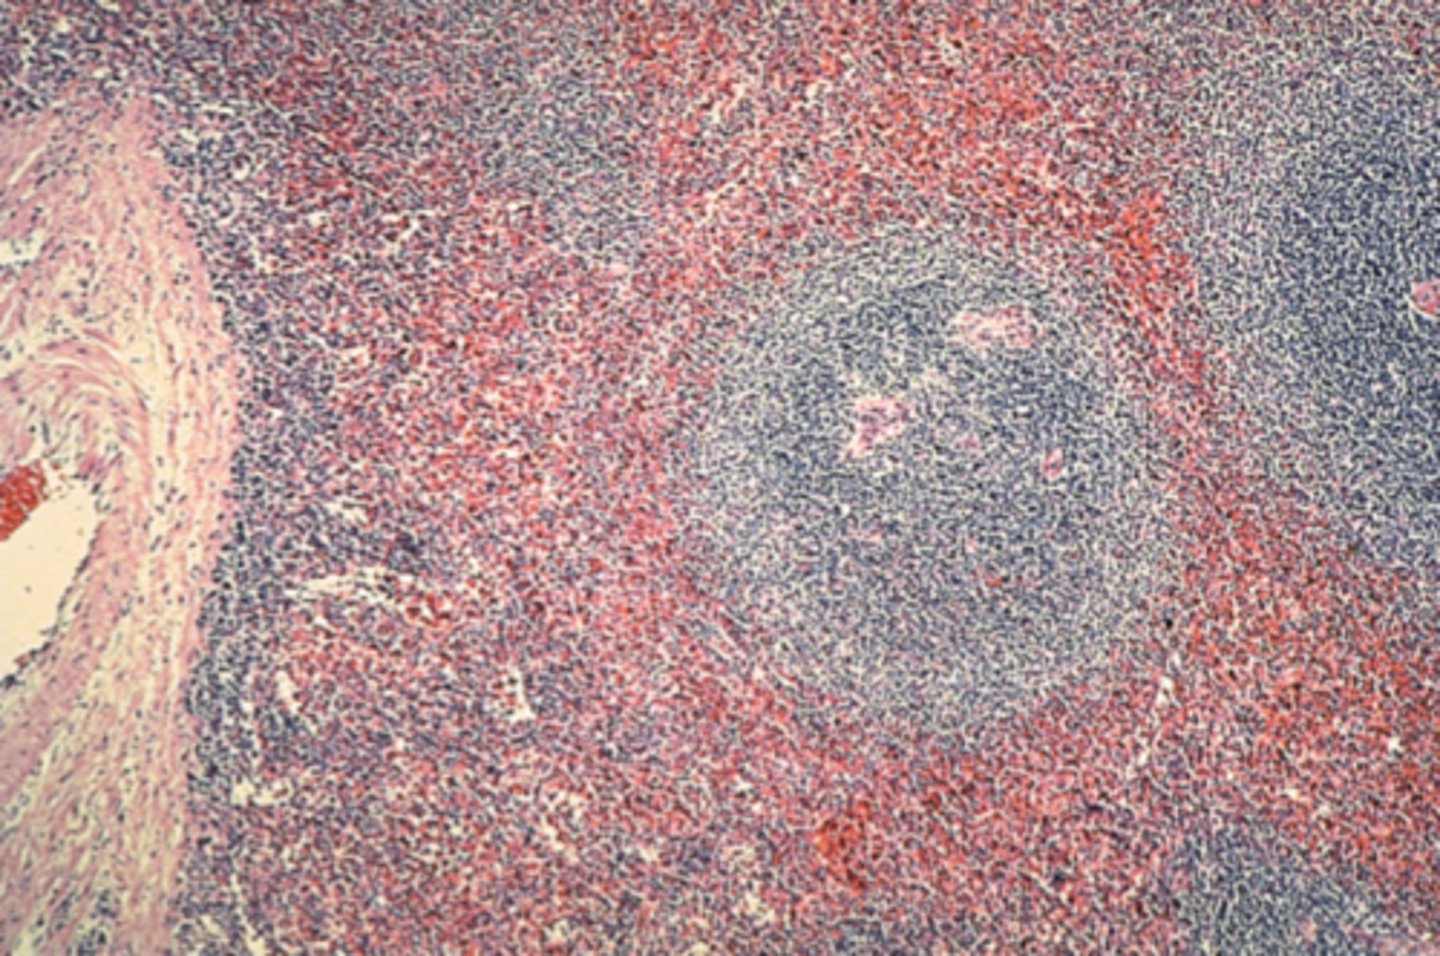

Spleen

What is this?

White pulp in spleen

What is it pointing at?